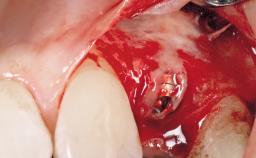

The video demonstrates implant placement using a surgical stent according to the principle of prosthodontically driven implant placement. The deficient ridge is augmented with locally harvested autologous bone chips, a superficial layer of xenogenic DBBM particles and a resorbable collagen membrane. The surgery is completed with a precise, tension-free primary wound closure.

Bone Augmentation Horizontal|Simultaneous

Augmentation Materials Autogenous chips|Xenogenous|Membrane

Bone Volume Deficient horizontally, allowing simultaneous augumentation